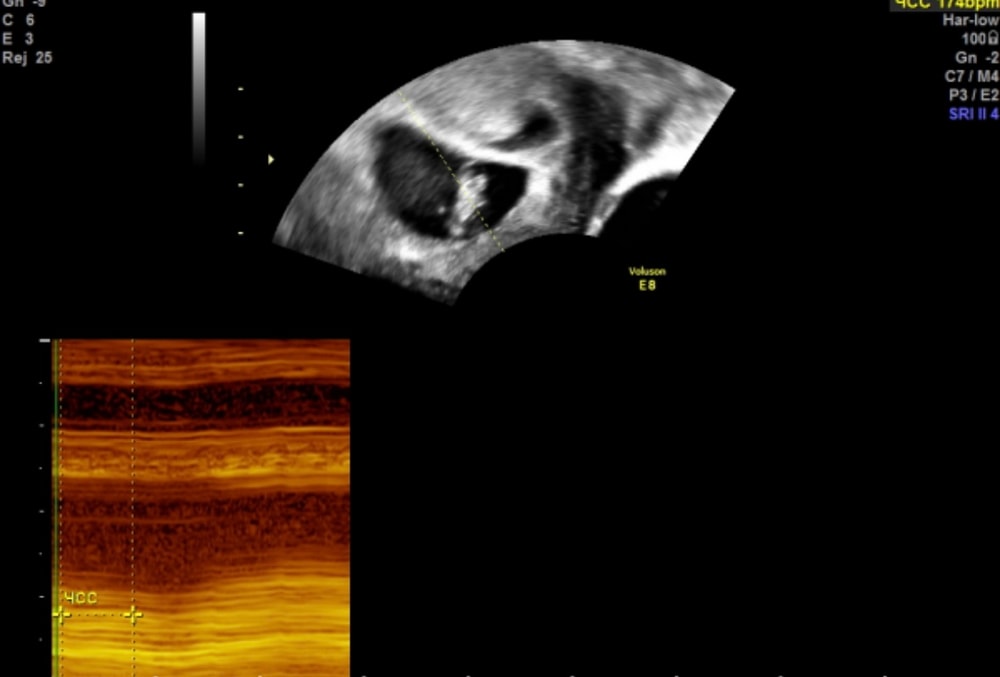

Вчера переделала узи, услышали сердцебиение. Рядом с ПЯ врач увидела полость, сказала, это либо отслойка/гематома, либо второе плодное яйцо, но пустое.

Как вам кажется, что это, гематома, или второе ПЯ?